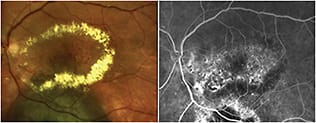

Figure 3. Color fundus photo (left) of an eye with AMD that was unresponsive to intravitreal pharmacotherapy, showing retinal exudation and scarring. A Navilas treatment plan (right) for grid laser maculopexy, based on retinal thickness map from an OCT scan of the same eye imported into the Navilas system, overlaid on the FA image, and aligned on the foveal center of the same eye. False color (red) shows retinal thickening.

Figure 4. Fluorescein angiogram (left) of the same eye in Figure 3, showing exudation and scarring. A Navilas treatment plan (right) for grid laser maculopexy based on the FA image.

Figure 5. Color fundus photo (left) of an eye with circinate retinopathy that underwent previous laser photocoagulation following radiation for choroidal melanoma (black). Early-phase fluorescein angiography image (right) showing retinal scars from previous laser photocoagulation.

Figure 6. Late-phase fluorescein angiography image of the same eye in Figure 5, showing late leakage next to retinal scars from previous laser photocoagulation. The large yellow circle represents the “no treatment zone,” and the small yellow circles are target laser spots. A Navilas treatment plan (right) for grid laser, based on a retinal thickness map from an OCT scan of the same eye imported into the Navilas system, overlaid on the FA image. False color (red) shows retinal thickening, although overt leakage is absent on FA.